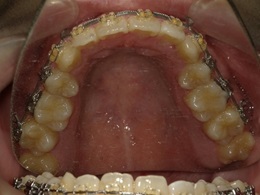

上顎治療中

上顎治療後